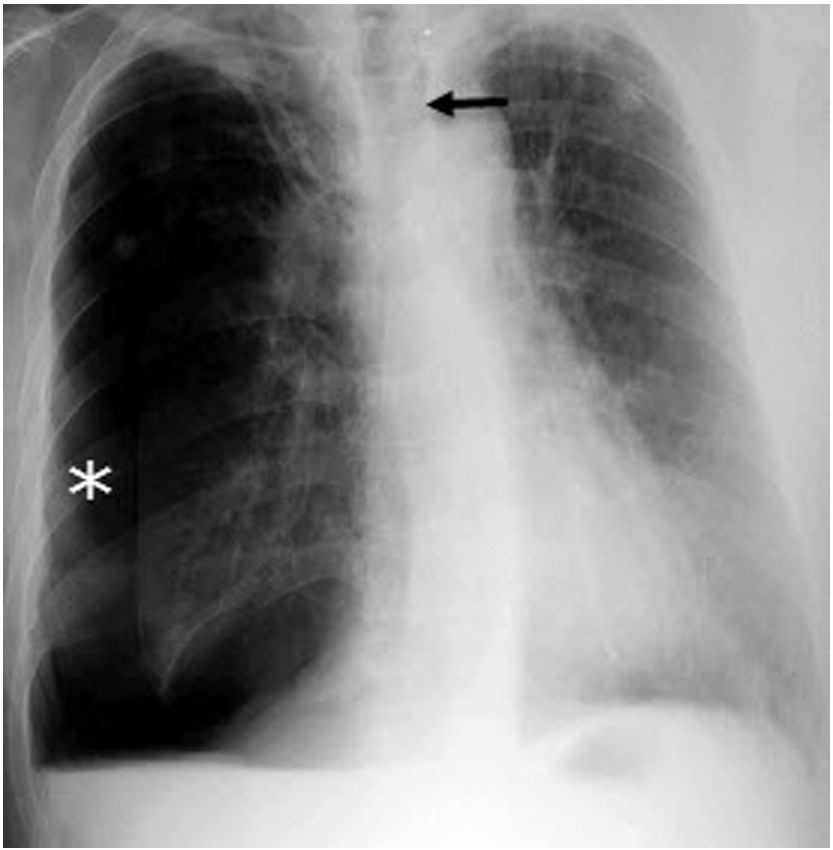

Mounier-Kuhn syndrome, or tracheobronchomegaly, is a rare clinical and radiological disorder characterized by severe tracheobronchial dilatation and recurrent lower respiratory tract infections. This syndrome diagnosis is made by our qualified and specialist doctors with the help of tomography, which is done on computers and bronchoscopy. Also, they asked the patient to do some lung function tests to directly go to the disease because there are many lung disorders and their symptoms will resemble this disorder, so many types of tests are required to diagnose it accurately so as not to go through with any complications.